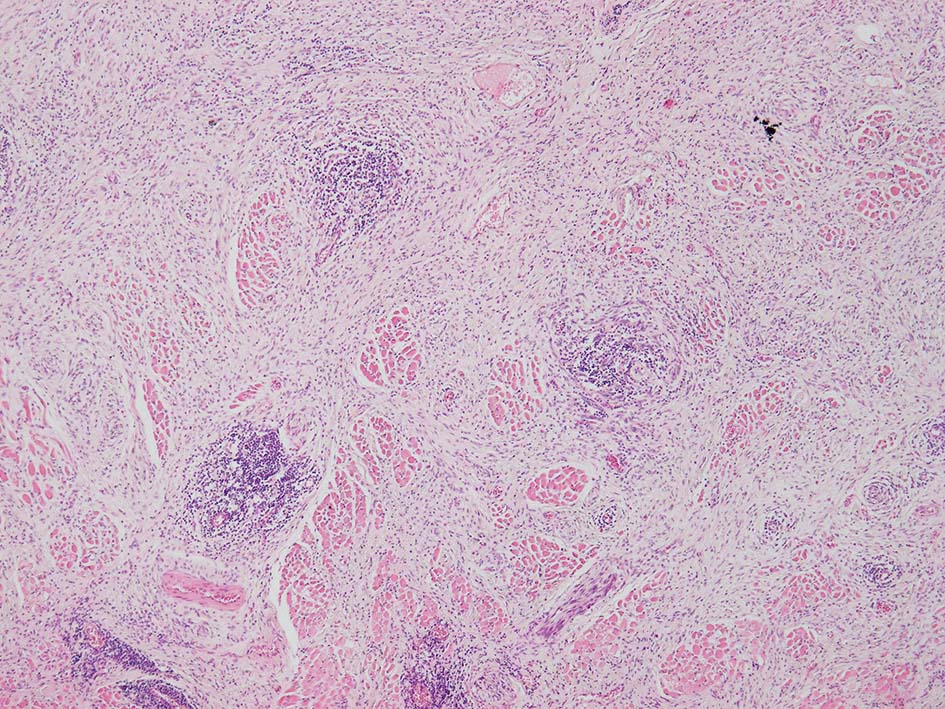

紡錘形異型メラノサイトが著明な間質反応(desmoplasia)を伴い増殖する特殊な色素性病変。*1. desmoplastic neurotropic melanomaは, desmoplastic melanomaのうち神経向性(neurotropism:神経周囲侵襲像)がめだつものでReedら*2が最初に報告した。

いずれも腫瘍細胞の異型性が乏しく, 背景の間質反応がめだつこと, メラニンの存在が目立たないことが特徴である。

病理組織所見*4

リンパ濾胞が細血管周囲に形成され, この部分に異型といえる細胞が増加している(S100+)